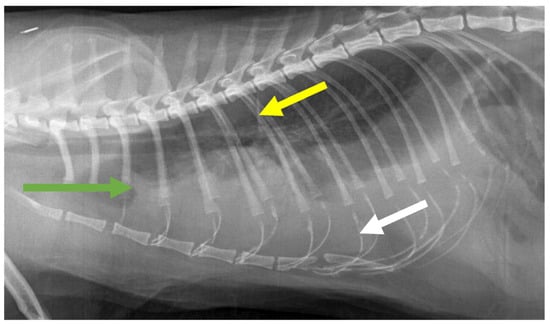

7.4. Diagnostic Imaging in FIP

7.4.1. Routine Imaging: Ultrasonographic and Radiographic Findings

7.4.2. Advanced Imaging of the CNS: MRI and CT

| Summary of Section 7: Diagnosis of FIP; Section 7.4: Diagnostic imaging in FIP: No specific ultrasonographic or radiographic findings exist for FIP. Ultrasonography (in particular) and radiography can show the presence of effusions. Pneumonia due to FIP that is occasionally reported can be associated with radiographic changes. Ultrasonography can reveal abdominal lymphadenomegaly or lymphadenopathy and/or abnormalities of the liver, spleen, intestines and/or kidneys (which can include a medullary rim sign), depending on which organs are affected. Imaging can also be of use to the direct sampling of abnormal tissues, e.g., fine-needle aspirate for cytology examination to reveal non-septic pyogranulomatous inflammation, or ultrasound-guided needle core (e.g., tru-cut) biopsies can be collected and submitted for histopathology. When a cat is showing neurological signs, the imaging of the brain by magnetic resonance imaging, if available, with contrast, can be useful to demonstrate neurological abnormalities (such as obstructive hydrocephalus, syringomyelia, foramen magnum herniation and marked contrast enhancement of the meninges, third ventricle, mesencephalic aqueduct, and brainstem). A description of computerised tomography findings in cats with neurological FIP has not been published, but MRI is likely to be more sensitive in the detection of subtle intraparenchymal lesions. Advanced imaging of the central nervous system is indicated before performing cerebrospinal fluid sampling to assess the potential risk of herniation. |